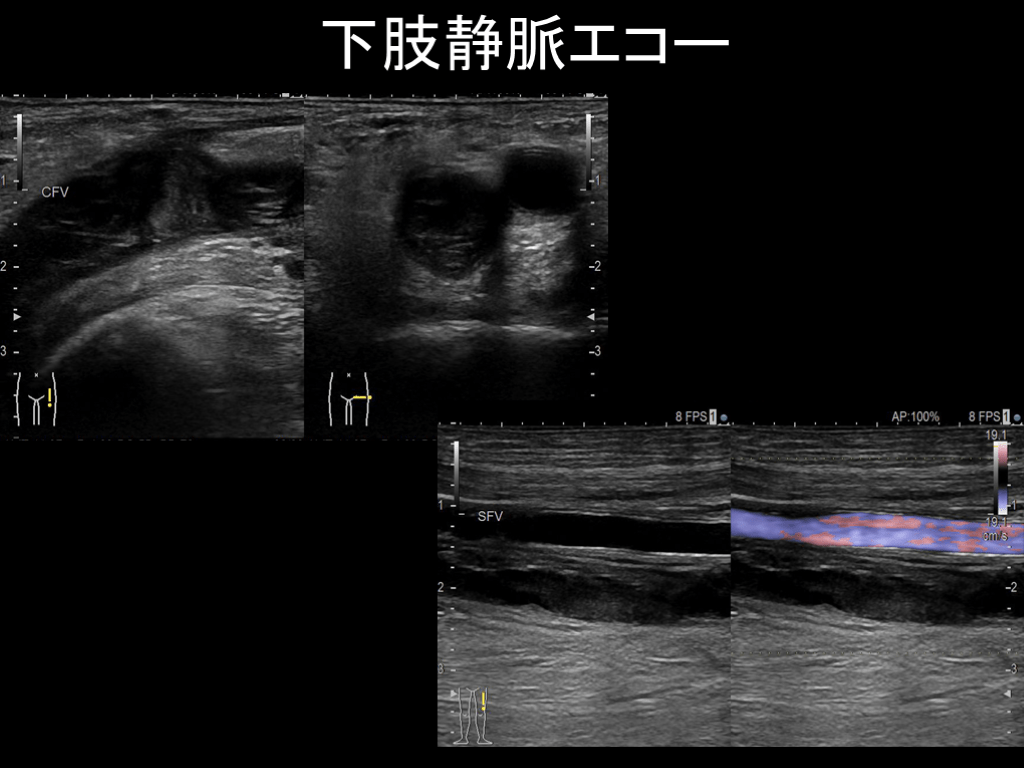

#25.

下肢静脈エコー

高齢者における浮腫の評価